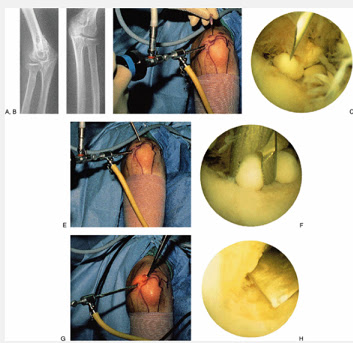

2. Key Hole Surgery(Arthroscopy)- If the patients predominant symptoms are “locking” and loss of movement , this can be helped by doing a key hole operation to remove loose bodies from joint. This immediately alleviates the symptoms.

Arthroscopic (Key Hole Surgery) involves two small stab incisions are made in the elbow through which small telescope and instruments are used to remove loose bodies, inflammatory tissue or bony spurs.

Elbow Arthroscopy